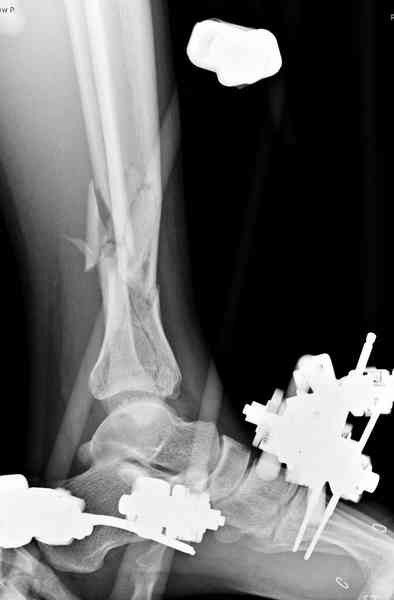

Пострадавшему 21 г., травма скоростная, после I&D с расширением раны, на бедре сделана операция ретроградным интрамедуллярным штифтом, остеосинтез с частичной резекцией надколенника и ушивание собственной связки.

На голень наружный фиксатор, рану на бедре ушили (рана была изнутри кнаружи всего 2 см). По протоколу травматических больных, до операции обследован ангиографически, (у больного дистально не смогли определить пульсацию) сосудистый хирург подтвердил проходимость на всем протяжении магистрального сосуда нижней конечности по снимкам ангиограмм.

В настоящее время больной в реанимации по поводу Черепно Мозговой Травмы и состояние улучшается. Запланировал ушивание раны в пятницу, если позволит состояние мягких тканей и при отсутстви отека возможно удастся просунуть перкутанномедиальную пластину.